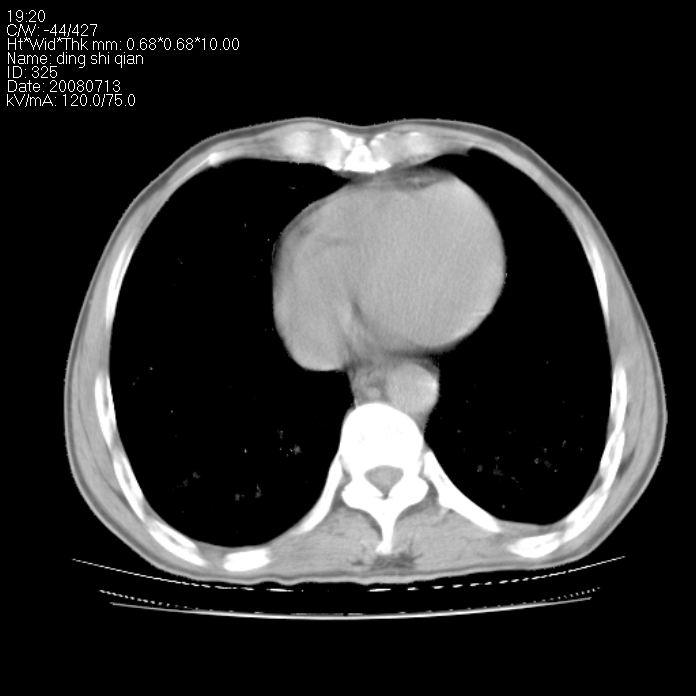

标题: CT14654:男 50岁 近来胸痛 [打印本页]

标题: CT14654:男 50岁 近来胸痛

右侧上肺块状软组织影,浅分叶,边缘毛刺证,与胸膜粘连,考虑:周围性肺癌

右肺上叶周围型肺癌可能性大。

右侧上肺块状软组织影,浅分叶,边缘毛刺证,与胸膜粘连,考虑:周围性肺癌!支持!

典型右肺周围型肺癌

首先考虑周围性肺癌,建议强化或穿刺明确

考虑: 右肺上叶周围型肺癌可能性大.

右肺上叶周围型肺癌。